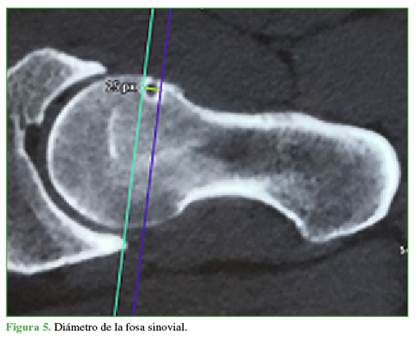

Características morfológicas de la FS: se utilizaron los cortes oblicuos axiales de la TC o la artro-RM para analizar los siguientes parámetros: 1) Profundidad: medida con una tangencial desde el borde anterior femoral y el punto más profundo de la FS (Figura 4); 2) Diámetro: medido con una tangencial desde el borde proximal femoral y el punto más distal de la FS (Figura 5); 3) Forma: redonda, oval o polilobulada y 4) Bordes: completo (quiste) o incompleto (muesca).

La distancia promedio de la FS al centro de rotación de la cabeza femoral fue de 12,5 mm (rango 6-28); la profundidad, de 6,3 mm (rango 2-14); y el diámetro, de 6 mm (rango 2-12). El 82,1% de las FS tenía un borde completo y el 17,9%, bordes incompletos. La forma era redondeada en el 78,6% (22 casos), ovalada en 3 casos (10,7%) y polilobulada en otros 3 casos (10,7%).